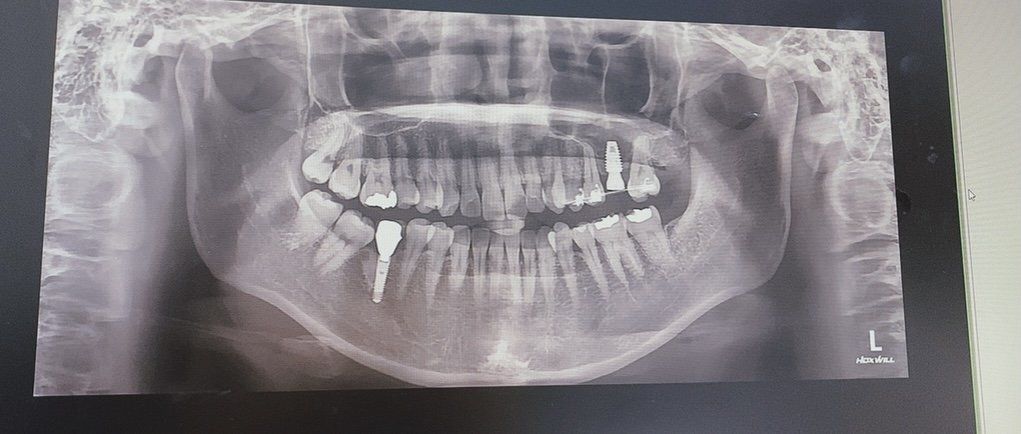

최종적으로 붙이기 전, 제가 임플란트인지 크라운이 흔들리는것같다 라고 이 불편함감에 대해서 담당의사분에게 전달하였고, 들은바로는 이 엑스레이를 보여주시며 뼈가 잘 생성되고있으며 임플란트는 움직이지 않는다. 주위의 치아 치주인대가 거의 없기에 그렇게 느끼는 것일 수있다. 자리를 잡으며 괜찮아질것이며, 한달정도 사용해 보면 괜찮아질것이다. 라고 하였어요.

• 1번 째 사진

• 2번 째 사진

좌측 제 1대구치에 임플란트 상황을 보면 나빠보이지 않습니다. 물론 이 자료 이외에도 dental CT가 있다면 더 정확하겠지만 사진상으로 큰 문제는 없습니다. 주치의 선생님 말씀대로 임플란트는 자연치와 달리 치주인대가 없기 때문에 동요도를 느끼는 것은 비정상적인 반응이긴 합니다. 하지만 한가지 걸리는 것은 임시치아 당시 3번이나 떨어졌다는 것이 마음에 걸립니다. 보통 3번이 떨어졌다면 환자분의 구강 악습관이 존재하거나 임플란트의 방향이 문제가 될수도 있고 교합양상이나 다른 기타 검사 등을 한번 해보는 것도 나쁘지 않습니다.